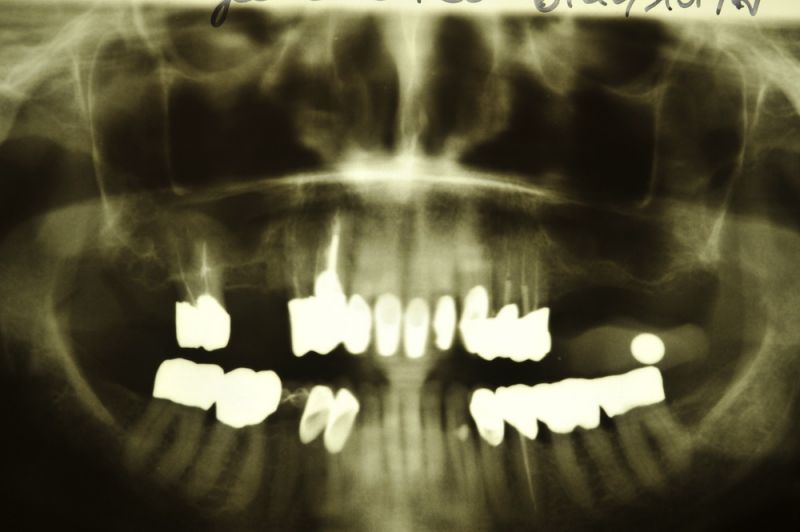

76 jährige Patientin mit 2 Implantaten und externem Sinuslift

Im Verlauf der Jahre ist es an verschiedenen Zähnen des Oberkieferseitenzahnbereichs zu Defekten und Beschwerden gekommen, die eine Entfernung mehrerer Seitenzähne nach sich gezogen hat und noch nach sich ziehen wird.

Am heutigen Tag sind in regio 26 und 27 zwei Implantate mit einem externen Sinuslift versorgt worden. Die Besonderheit des Eingriffs liegt darin, dass im Oberkieferseitenzahnbereich, bei einer noch vorhandenen Restknochenhöhe von wenigen Millimetern, zwei Implantate gesetzt und gleichzeitig eine Aufdoppelung des vorhandenen Restknochenangebots, durch die Schaffung eines Raumes zwischen knöcherner Abgrenzung der Kieferhöhle und der in die Kieferhöhle hinein verdrängten Kieferhöhlenmembran geschaffen werden konnte.